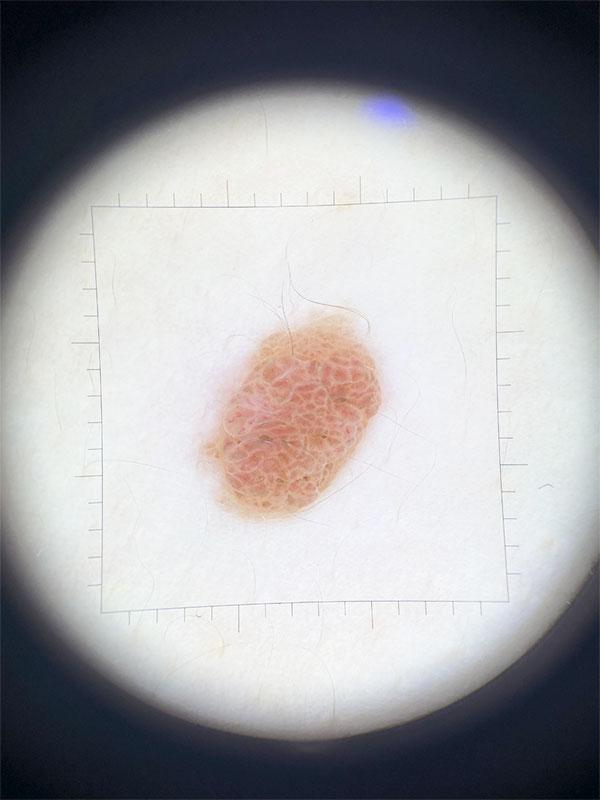

Самообследование родинок методом АКОРД поможет заблаговременно обратить внимание на образование, склонное к злокачественному перерождению:

- А – асимметрия

- К – край (неровный)

- О – окрас (неоднородный)

- Р – размер (более 6 мм)

- Д – динамика (изменение размеров, цвета, формы)

Если Вы заметили изменения родинки хотя бы по одному признаку – это повод обратиться к врачу дерматологу или дерматоонкологу и провести цифровую дерматоскопию. Диагностированная на начальной стадии онкология кожи имеет хорошие перспективы на полное выздоровление. Внимание к ранней диагностике, своевременный скрининг новообразований кожи – безусловно, является большим шагом к преодолению страшных последствий рака и уменьшению уровня смертности от онкологии кожи! Спасибо всем, пациентам и врачам, кто присоединился к проекту – День меланомы, вместе мы поборем рак кожи!